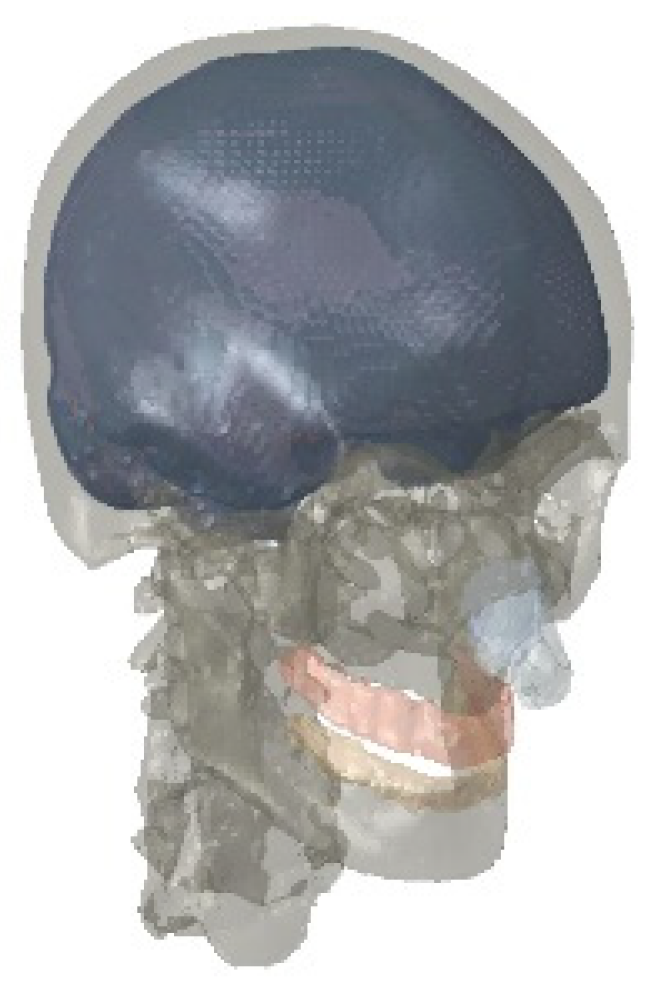

2.1. Finite Element Model of the Head

2.1.1. Model Construction